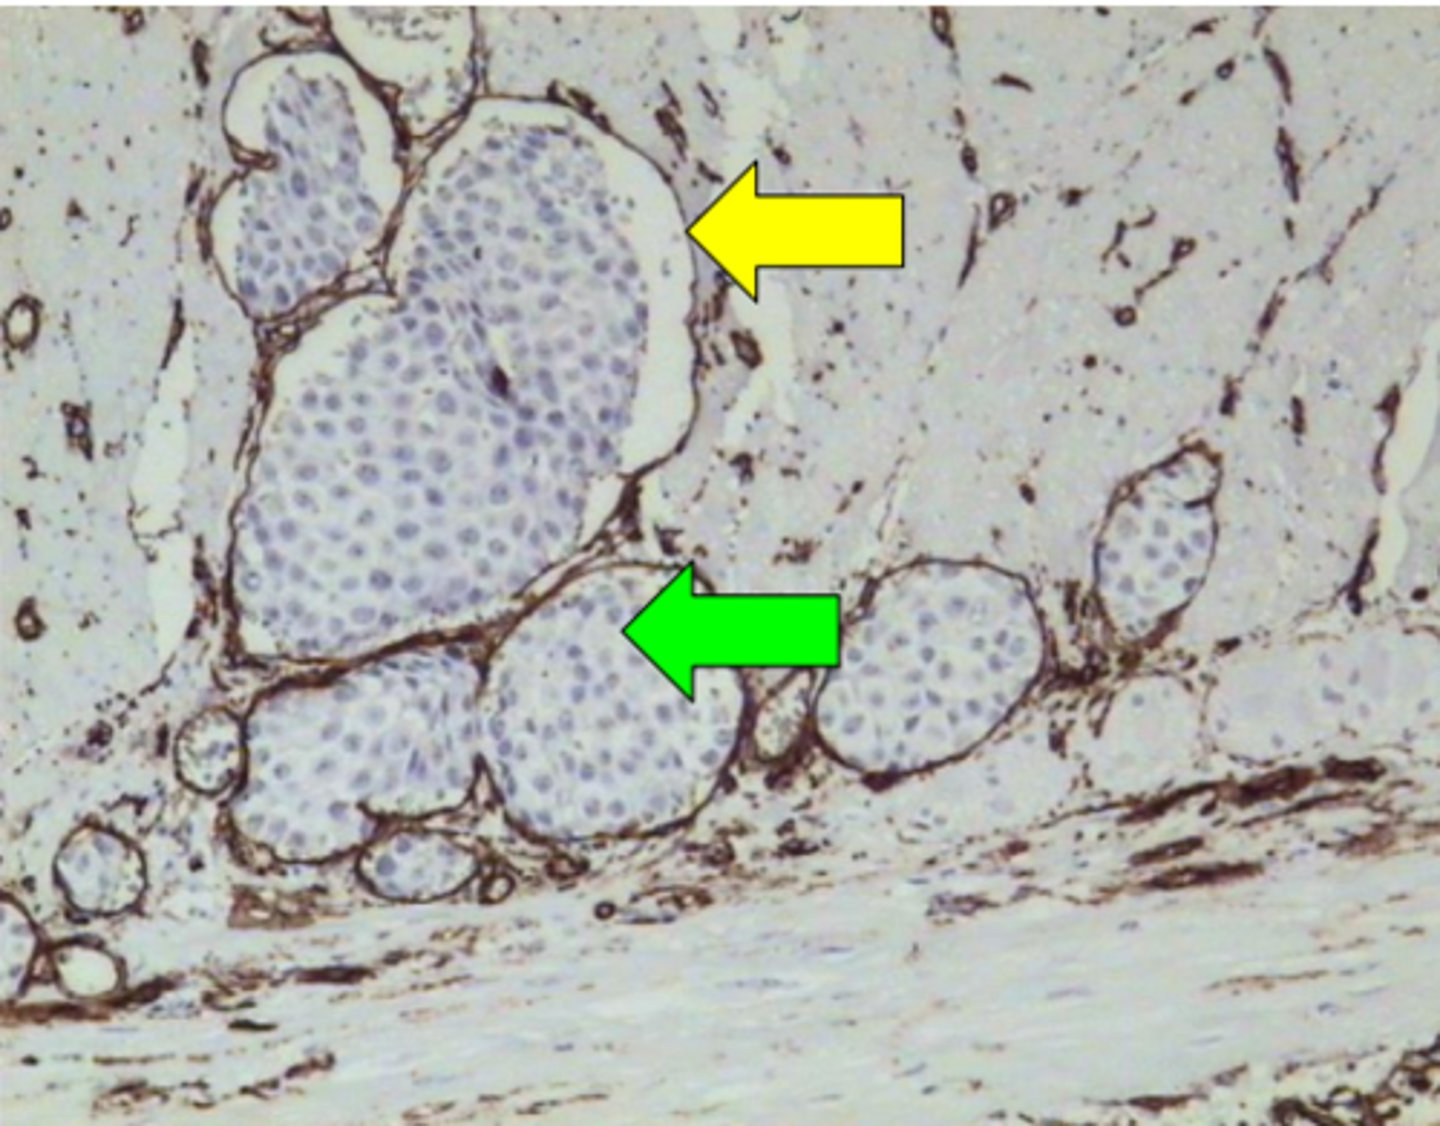

Melanomas metastāze zarnas sieniņā. Anti - CD34

Melanomas metastāze zarnas sieniņā. Anti - HMB-45